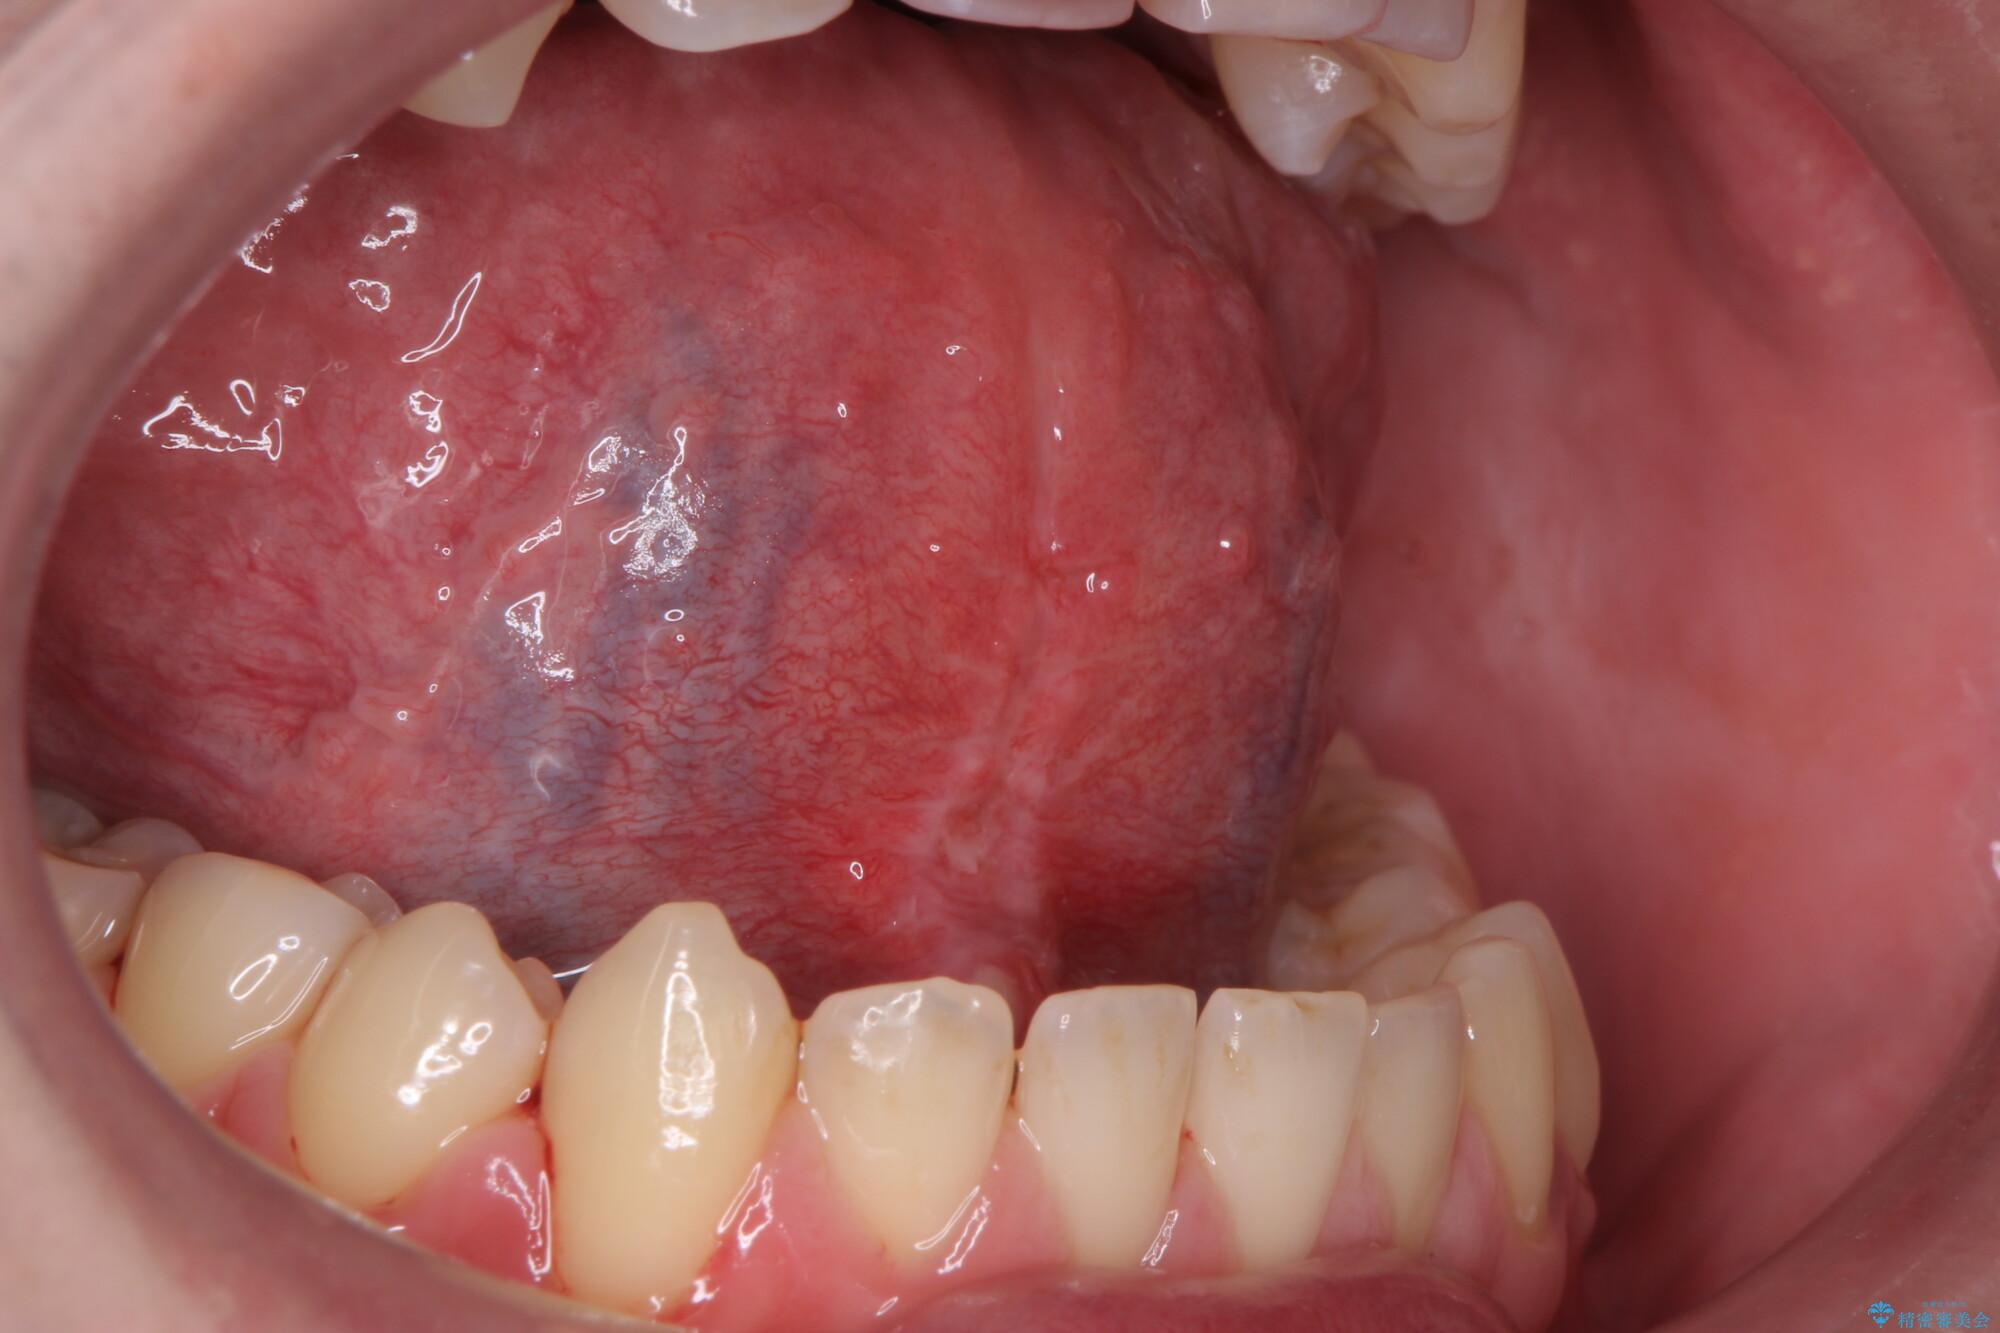

治療前

舌小帯を切除し滑舌を治したい 治療前画像 舌小帯を切除し滑舌を治したい 治療前画像